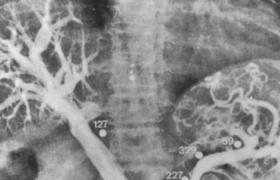

脑血管造影